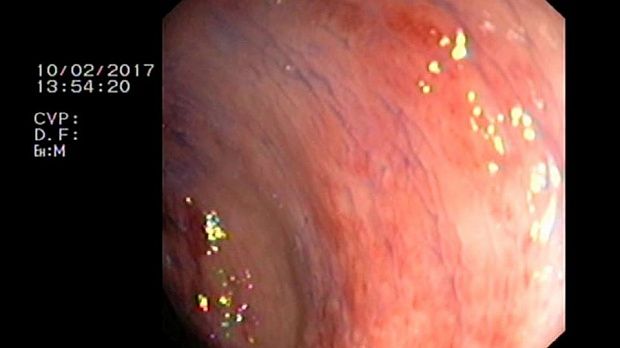

2 мл ( это мин сум, а мы делаем до 10 мл 3% перекись+200 мл физ раствора